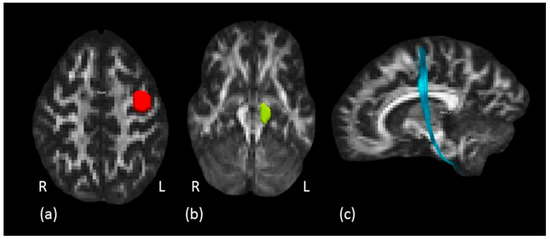

Structure of the Motor Descending Pathways Correlates with the Temporal Kinematics of Hand Movements

The projection system, a complex organization of ascending and descending white matter pathways, is the principal system for conveying sensory and motor information, connecting frontal and sensorimotor regions with ventral regions of the central nervous system. The corticospinal tract (CST), one of the [...] Read more.

The projection system, a complex organization of ascending and descending white matter pathways, is the principal system for conveying sensory and motor information, connecting frontal and sensorimotor regions with ventral regions of the central nervous system. The corticospinal tract (CST), one of the principal projection pathways, carries distal movement-related information from the cortex to the spinal cord, and whether its microstructure is linked to the kinematics of hand movements is still an open question. The aim of the present study was to explore how microstructure of descending branches of the projection system, namely the hand motor tract (HMT), the corticospinal tract (CST) and its sector within the internal capsule (IC), can relate to the temporal profile of reaching and reach-to-grasp movements. Projection pathways of 31 healthy subjects were virtually dissected by means of diffusion tractography and the kinematics of reaching and reach-to-grasp movements were also analyzed. A positive association between Hindrance Modulated Orientation Anisotropy (HMOA) and kinematics was observed, suggesting that anisotropy of the considered tract can influence the temporal unfolding of motor performance. We highlight, for the first time, that hand kinematics and the visuomotor transformation processes underlying reaching and reach-to-grasp movements relate to the microstructure of specific projection fibers subserving these movements. Full article

Show Figures

Figure 1